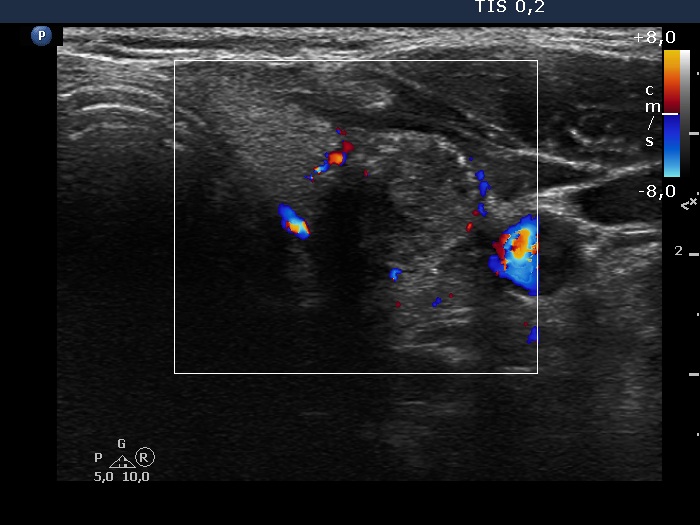

100 consecutive cases of papillary cancer - case 072 (ultrasonographic picture 7)

Left lobe, transverse scan, color Doppler mode. The nodule is avascular. The vessels are close to the nodule but are located outside the lesion.